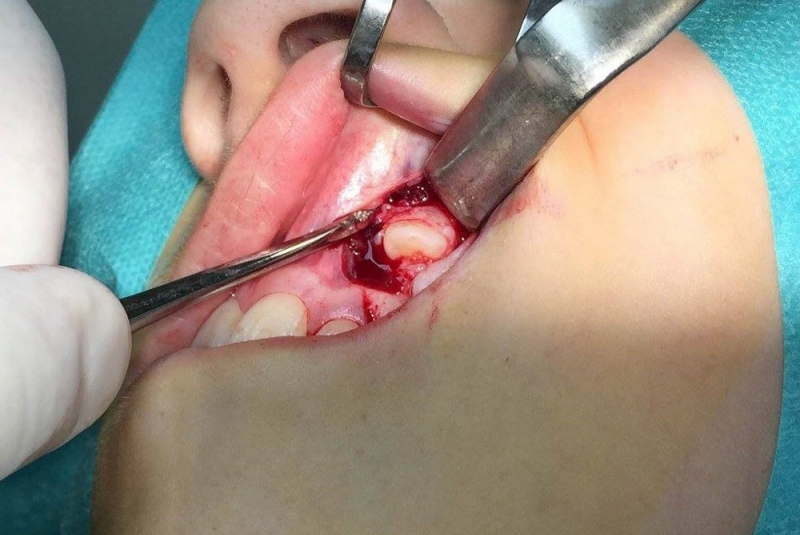

- Chirurgické extrakcie

- Cystectomia